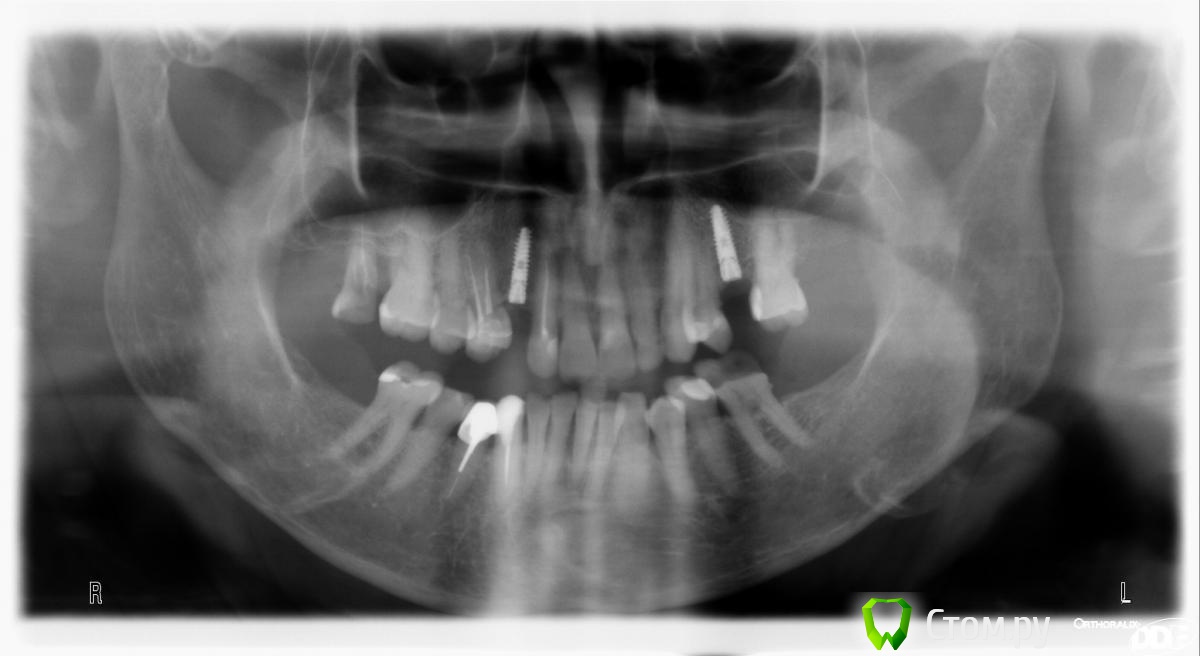

Rusty Опубликовано 23 сентября, 2014 Поделиться Опубликовано 23 сентября, 2014 Доброго дня. Подскажите, что за винты. Первый устанавливался около 7 лет назад в Москве. На следующем снимке импланты устанавливались в начале 90-х в Москве. Ссылка на комментарий

SDC Опубликовано 23 сентября, 2014 Поделиться Опубликовано 23 сентября, 2014 (изменено) Нобель и 2 Ксайва.Xive 3.4 справа и 3.8 слеваИ условий для протезирования нет...и на нобеле тоже Изменено 23 сентября, 2014 пользователем SDC 1 Ссылка на комментарий

faity Опубликовано 24 сентября, 2014 Поделиться Опубликовано 24 сентября, 2014 (изменено) нобель удалять инфа 100%для протезирования на ксайве я бы брекеты поставил Изменено 24 сентября, 2014 пользователем faity Ссылка на комментарий

Дмитрий Никитюк Опубликовано 25 сентября, 2014 Поделиться Опубликовано 25 сентября, 2014 нобель удалять инфа 100% для протезирования на ксайве я бы брекеты поставил Зачем так радикально. Что касается Нобеля, то там проще мудрость убрать и подвинуть 36 с 37 назад немного. С Ксайвами нужно фото смотреть, по факту места может быть больше, чем на ОПТГ. В любом случае, можно сделать временные коронки, раз имплантат поставили, значит темпбейз помещается. Берем темпбейз, делаем времяшку на винтовой фиксации вплотную к зубам. Дальше устанавливаем ортодонтические сепараторы. Получаем щели, добавляем контактные пункты, опять сепараторы, и так пока не получим достаточно места. Естественно нужно понимать, что куда будет перемещаться, чтобы не получить проблем в виде ротаций и скученности во фронтальном участке. А с перемещением моляра дистально таким способом проблем вообще не будет. 6 Ссылка на комментарий

SDC Опубликовано 25 сентября, 2014 Поделиться Опубликовано 25 сентября, 2014 Зачем так радикально. Что касается Нобеля, то там проще мудрость убрать и подвинуть 36 с 37 назад немного. С Ксайвами нужно фото смотреть, по факту места может быть больше, чем на ОПТГ. В любом случае, можно сделать временные коронки, раз имплантат поставили, значит темпбейз помещается. Берем темпбейз, делаем времяшку на винтовой фиксации вплотную к зубам. Дальше устанавливаем ортодонтические сепараторы. Получаем щели, добавляем контактные пункты, опять сепараторы, и так пока не получим достаточно места. Естественно нужно понимать, что куда будет перемещаться, чтобы не получить проблем в виде ротаций и скученности во фронтальном участке. А с перемещением моляра дистально таким способом проблем вообще не будет.Но может оказаться и так, что когда устанавливали, темп бейз проходил, а сейчас - нет. Но в любом случае необходима ортодонтическая подготовка. Или от импл., или на зубах. Ссылка на комментарий

red_butler Опубликовано 25 сентября, 2014 Поделиться Опубликовано 25 сентября, 2014 + 1 за ортодонтию, после удаления импланта прогнозируемы проблемы с семеркой Ссылка на комментарий